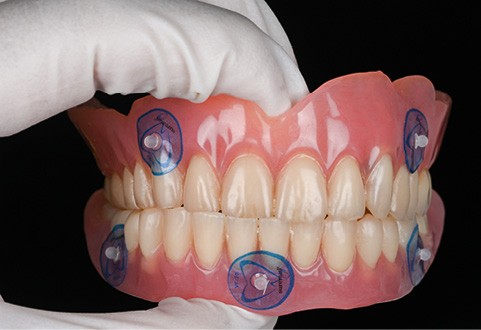

- appui muqueux : sa précision est inférieure. Réservé aux cas d’édentement total, il est conçu à partir d’un alignement avec une prothèse amovible complète comportant des marqueurs radio-opaques (fig. 5 à 8). Le risque d’imprécision est majoré par la dépressibilité de la muqueuse, la tuméfaction des tissus mous due à l’anesthésie, ou le positionnement initial en s’aidant de l’occlusion ;